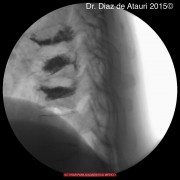

Puedes ver imágenes de una fractura y de la técnica quirúrgica de un caso real del 2015 tras este texto.